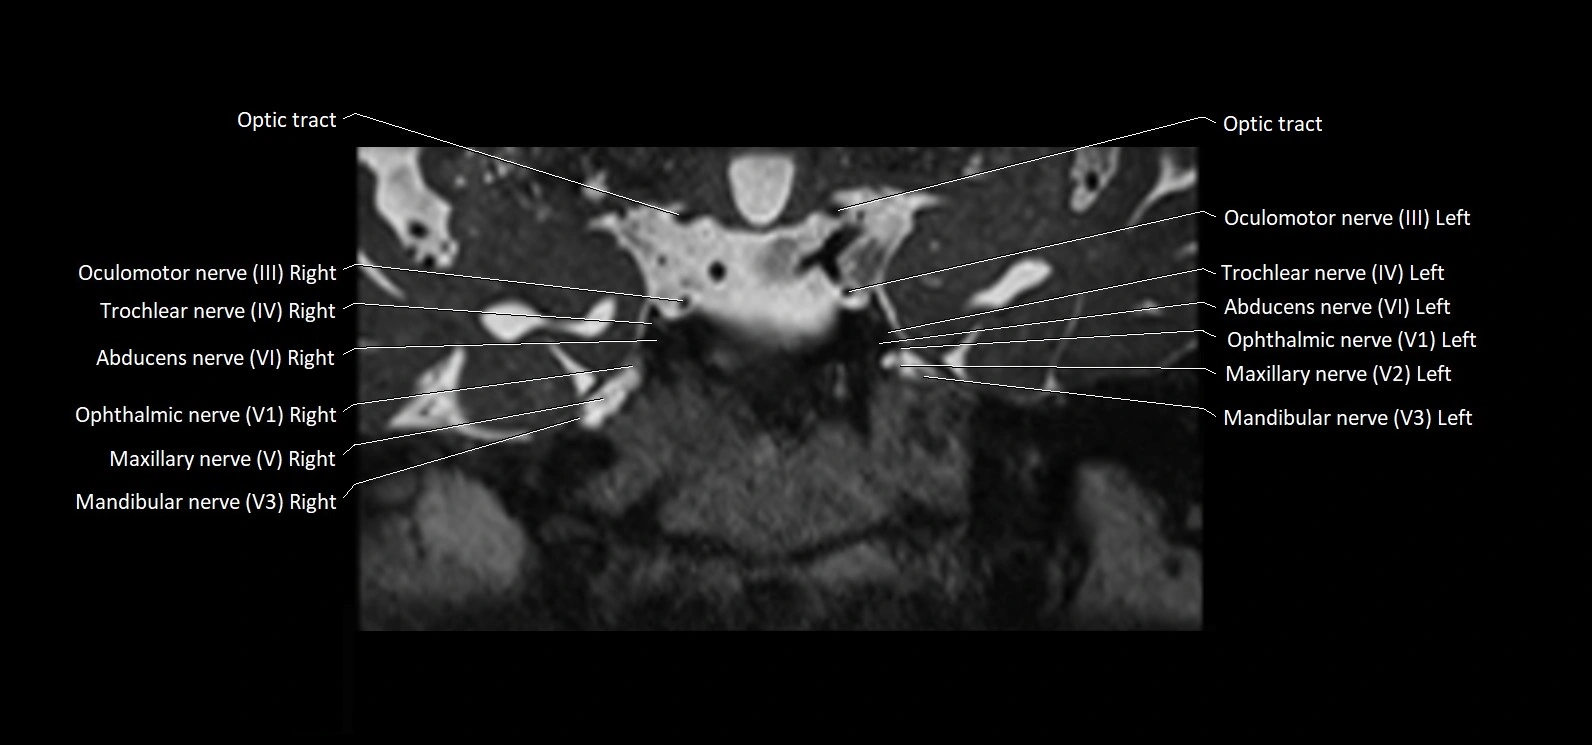

MRI Appearance

• The abducens nerve is a small, thin, linear structure

• Best visualized on high-resolution T2-weighted 3D MRI sequences (e.g., FIESTA or CISS)

• Seen as a hypointense (dark) line running from the brainstem at the pontomedullary junction, traversing the prepontine cistern, and entering Dorello’s canal under the petrosphenoidal ligament, then into the cavernous sinus, and finally the orbit

• May be challenging to visualize in standard MRI due to its small size

• Pathology may be inferred by absence, displacement, or enhancement of the nerve

MRI images

image